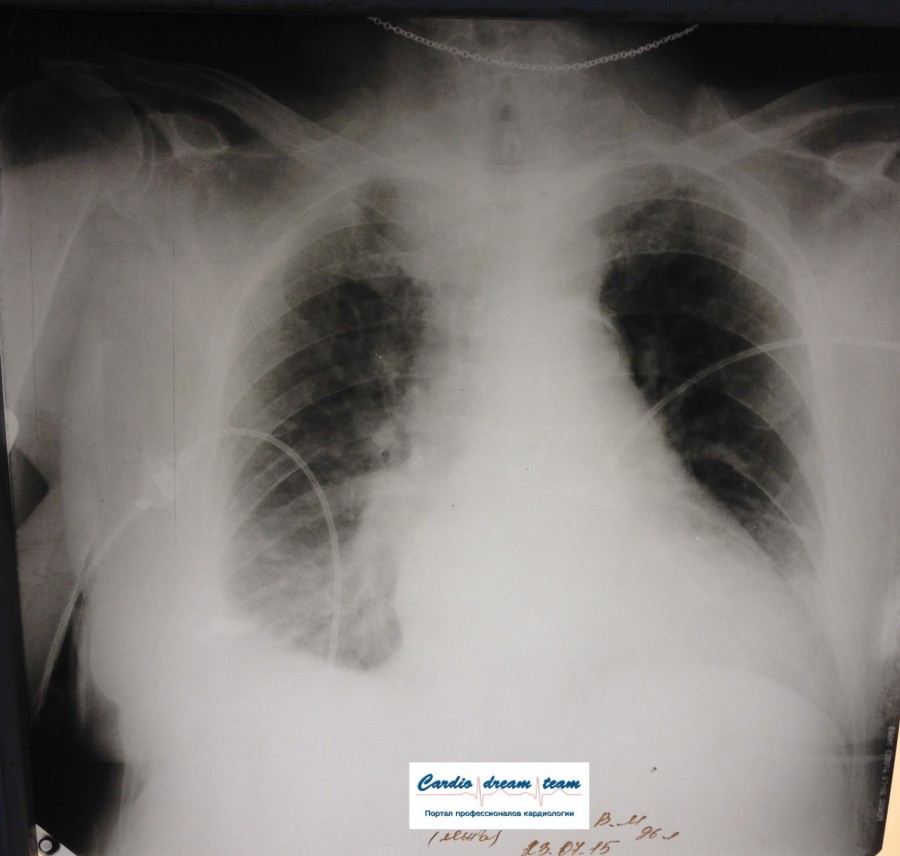

ОПИСАНИЕ:

Проведена рентгенография органов грудной клетки в прямой проекции, положение лежа, условия ПИТ

Легочные поля:

неравномерно прозрачны за счет сосудистого обогащения, в базальных отделах с обеих сторон, отмечается сгущение легочного рисунка, за счет гиповентиляции, в плевральных полостях жидкость

Легочный рисунок:

Изменен по смешанному типу: обогащен за счет сосудистого компонента, деформирован за счет склероза.

Корни:

бесструктурны, расширены за счет сосудистого компонента, обогащены

Синусы:

определяется наличие жидкости по линии 5 ребра

Сердце:

широко лежит на диафрагме отмечается расширение границ сердечной тени влево, вправо экг-электроды.

ЗАКЛЮЧЕНИЕ:

Рентген-признаки 2-х стороннего гидроторакса с гиповентиляцией базальных сегментов.. Признаки застоя по МКК 2 степени (умеренно выраженный). Пневмосклероз. Р-признаки гипертрофии левого желудочка сердца.

Склероз аорты.